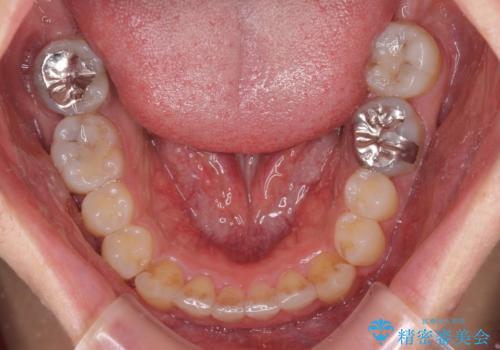

口が少し閉じにくい インビザラインによる非抜歯矯正

- 口元の突出感を治したいとのことで来院された患者様です。

上下顎ともにIPR(歯と歯の間を削る)と歯列全体の拡大によって口元が引っ込むように設計し、インビザラインにより治療を行うこととしました。

抜歯をして口元を下げなければならないほど出っ歯ではなかったため、少しずつ治療ゴールを変更しながら仕上げていきました。

気になっていた前歯の飛び出した印象は、最終的にはスッキリと引っ込み、大変満足していただきました。